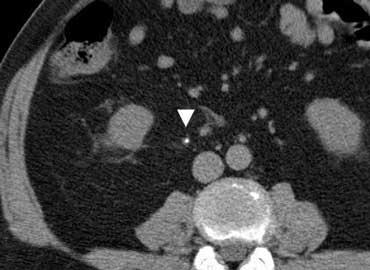

TRÁI: Phim bụng không chuẩn bị ở bệnh nhân bụng cấp, không thấy bất thường. PHẢI: CT thực hiện sau đó cho thấy các quai ruột non giãn (đầu mũi tên) không được nhìn thấy trên phim bụng không chuẩn bị do chúng chỉ chứa đầy dịch mà không có hơi trong lòng ruột.

Tắc ruột có thể không được phát hiện trên phim bụng không chuẩn bị nếu các quai ruột chỉ chứa đầy dịch mà không có hơi trong lòng ruột (hình minh họa).

Ngược lại, nếu phim bụng không chuẩn bị có dấu hiệu gợi ý tắc ruột thì siêu âm hoặc CT thường cần thiết để xác định nguyên nhân.

Do đó, phim bụng không chuẩn bị hiếm khi hữu ích, ngoại trừ trong phát hiện sỏi thận hoặc tràn khí phúc mạc.